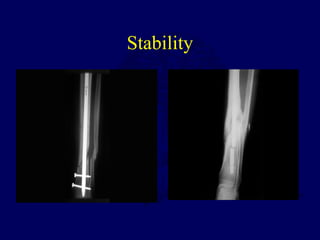

Stability

When

To

Interlock?

Loss of Alignment without

Interlocking Nails

• Spiral 7/22

• Transverse 0/27

• Metaphyseal 7/28

• Templeman CORR 1997